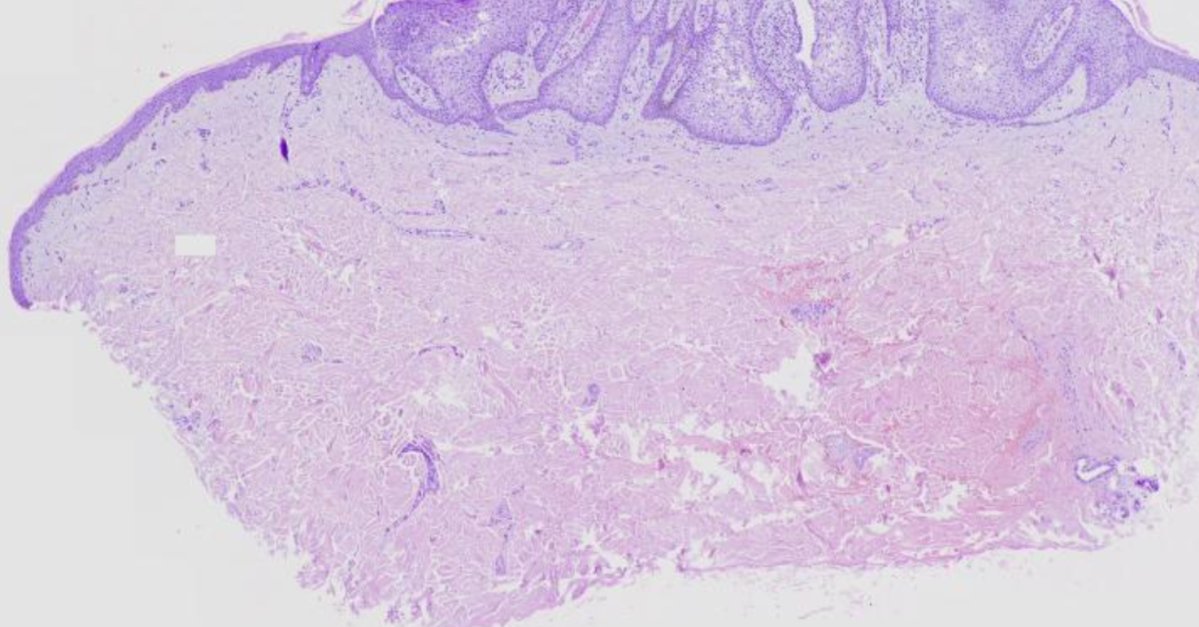

This case presents a diagnostic puzzle from the skin: a slowly enlarging erythematous papule in a 62-year-old man. Review the case to determine the most likely diagnosis. Contributed by Abhimanyu Tushir, MD: https://t.co/p2QdO4YnuD